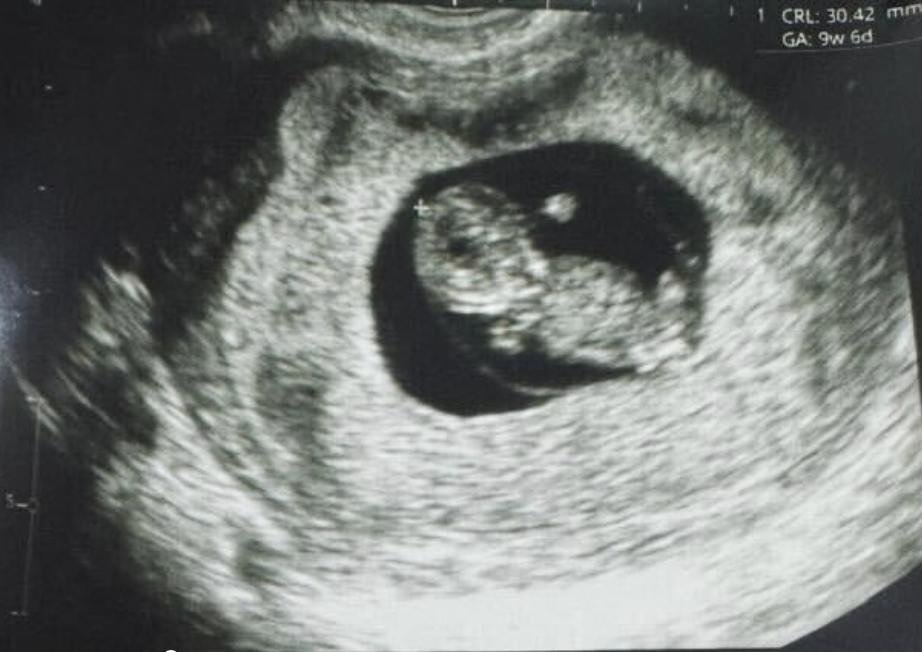

Родился первый в мире ребенок, для зачатия которого яйцеклетка зрелась вне тела.

Ребенок появился на свет в столице Перу.

Созревание яйцеклетки осуществляется вне тела женщины при помощи так называемых поддерживающих клеток яичника, которые получают в лаборатории из стволовых клеток.

В отличие от традиционного ЭКО, пациентке не требуется гормональная стимуляция, оказывающая значительную нагрузку на организм. Процедура занимает три дня вместо трех недель.